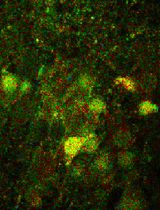

Figure 4. Characterization of cells at each differentiated stage. (A) Representative images of NESTIN+/PAX6+ and SOX2+/OCT4- neural stem cells (NSCs) on day 6 of differentiation. (B) Proportion of NESTIN+, PAX6+, SOX2+, and OCT4- NSCs on day 6 of differentiation. N = 7 cell lines, n = 3 replicates. (C) Representative images of OLIG2+/NKX6.1+ and OLIG2+/NKX2.2- MNPs on day 12 of differentiation. (D) Proportion of OLIG2+, NKX6.1+, and NKX2.2- MNPs on day 12 of differentiation. N = 2 cell lines, n = 3 replicates. (E) Representative images of MNX1+/ISLET1+ and MAP2+/CHAT+ spinal motor neurons (sMNs) on day 18 of differentiation. (F) Proportion of MNX1+, ISLET1+, MAP2+, and CHAT+ sMNs on day 18 of differentiation. N = 7 cell lines, n = 3 replicates. Scale bars: 100 μm. The quantification procedure is described in the Data analysis section. Data are presented by mean ± SEM.

j. Capture images using the confocal microscope. Representative immunostaining results for each differentiation stage are shown in Figure 4.